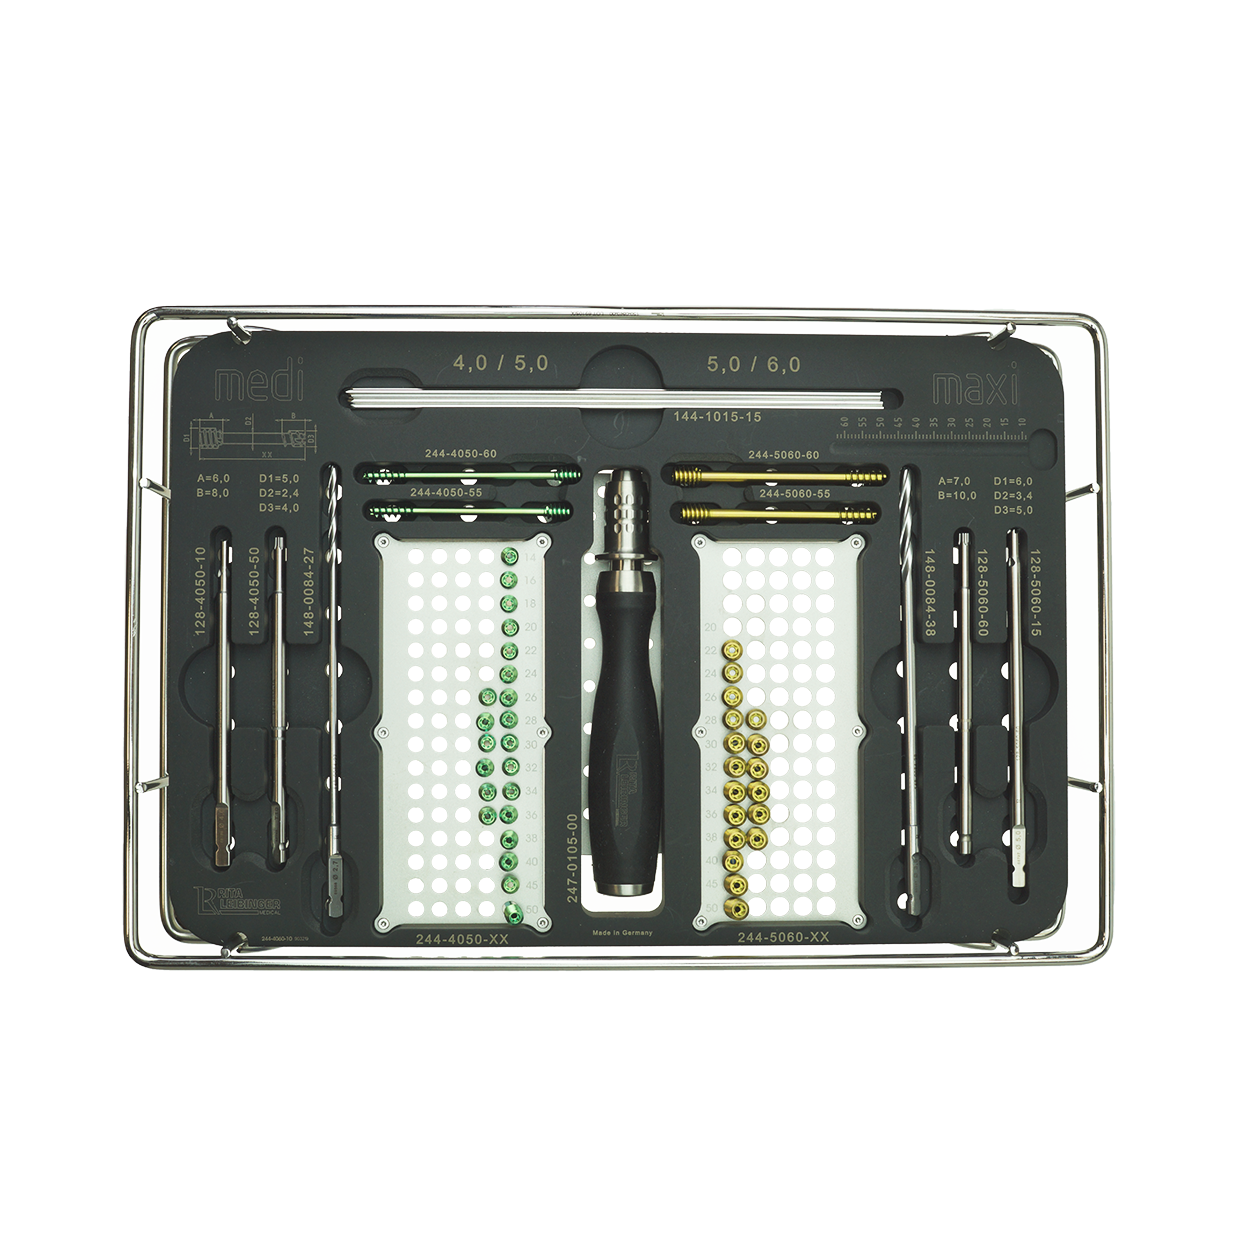

Moreover, LeiCOM offers compression screws in a variety of sizes (Micro, Mini, Medi, Maxi) and lengths, ensuring compatibility across a wide spectrum of patient sizes—from small to large breeds.

The LeiCOM Cannulated Compression Screws are engineered with stardrive screwheads, providing enhanced tightening torque in comparison to hexagonal screw heads. Complementing this, our system includes cannulated screwdriver shafts that are self-holding, simplifying the procedure and ensuring secure handling during use. These features contribute to precise and efficient fixation of the compression screws, promoting smoother surgical processes and reliable outcomes.